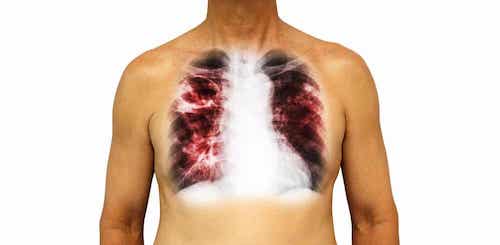

1. La pneumonie, l’une des maladies infectieuses les plus courantes

C’est une maladie bactérienne causée principalement par Streptococcus pneumoniae. Au début, la pneumonie affecte l’alparenchyme pulmonaire. Lorsque la pathologie passe à ses stades les plus graves, elle peut se propager du poumon au sang.

Pour le traitement de cette maladie, le médecin prescrit généralement des antibiotiques. Le calendrier d’administration sera adapté en fonction des caractéristiques du patient, ainsi que de celles de la maladie. Toutes les pneumonies ne se développent pas de la même manière.